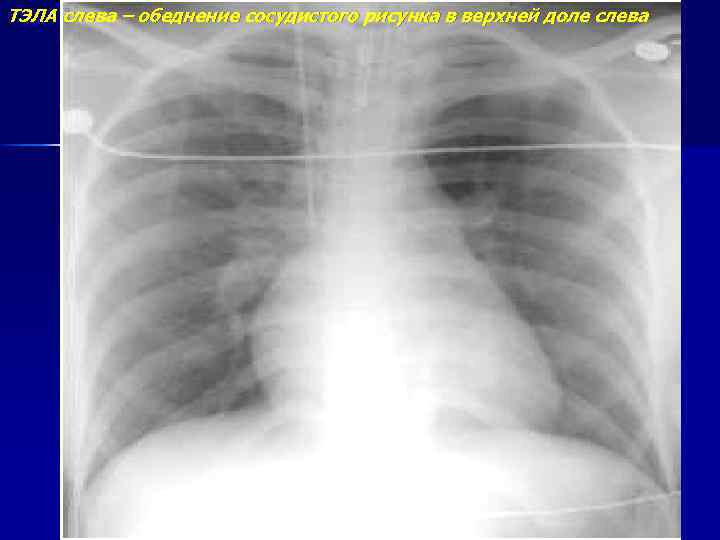

ТЭЛА слева – обеднение сосудистого рисунка в верхней доле слева

ТЭЛА слева (продолжение) КТ – тромб в левой ЛА